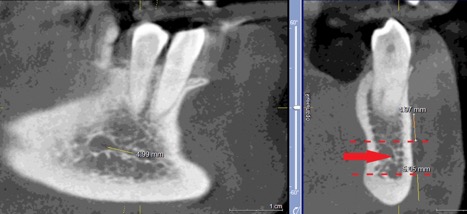

Данные осложнения происходят из-за повреждения резцовой петли – внутрикостного продолжения нижнелуночкого нерва (Рис. 1a и 1b), которая начинается от ментального отверстия и заканчивается индивидуально, как правило, на уровне латерального или центрального резца [1].

Рисунок 1а: КЛКТ. Панорамный реформат.

(Зеленая стрелка – резцовая петля, красная стрелка – подбородочное отверстие.)